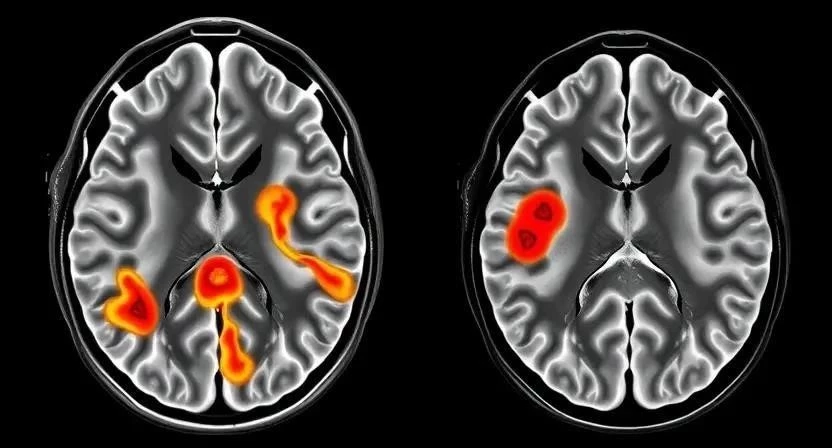

Диагностика вирусных инфекций требует комплексного подхода. Лабораторные исследования включают анализ крови (общий анализ, биохимический анализ, серологические тесты для выявления антител к вирусам), анализ спинномозговой жидкости (для выявления признаков воспаления и вируса), ПЦР (полимеразная цепная реакция) для обнаружения вирусной ДНК или РНК. Нейровизуализация, такая как МРТ (магнитно-резонансная томография) и КТ (компьютерная томография), позволяет оценить состояние мозга и спинного мозга. Важно помнить, что своевременная и точная диагностика – ключ к успешному лечению.

| МРТ | Оценка состояния мозга и спинного мозга |

| КТ | Оценка состояния мозга и спинного мозга |